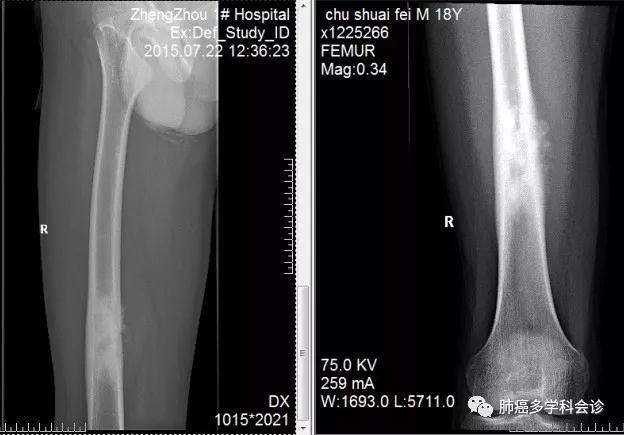

患者褚SF,男,20岁(2017年),2015年7月就医诊断为右侧股崩下股骨肉瘤,之后手术切除病变段股骨并植入义骨,接受 4 周期辅助化疗,之后间断复查胸部 CT。